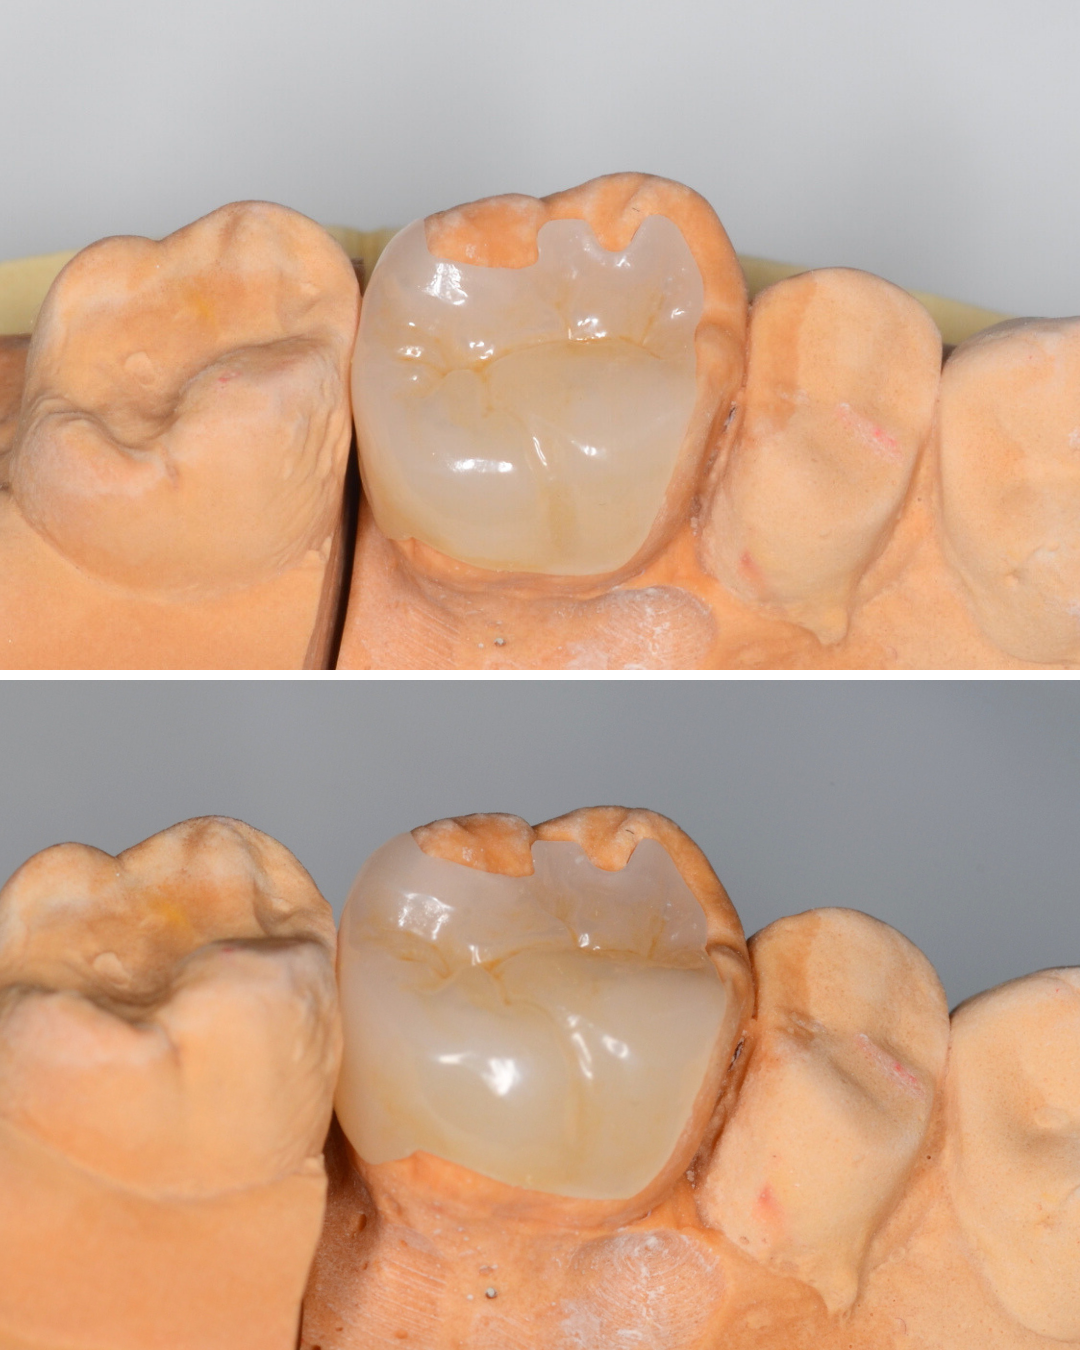

セラミックが精密にsetできるように、歯をトリミングします。

模型上で精密に製作します。